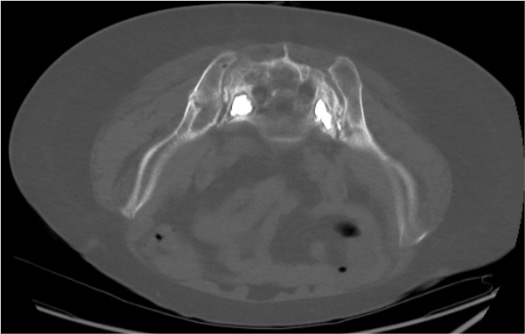

PMMA Cement Injection

- Target volume: 2–4 mL per Zone I alar fracture (2–8 mL range per literature); bilateral = 4–8 mL total

Cement-Related Complications

- Sacral nerve root injury — cement in foramina; S1 = foot drop; S2–S4 = bowel/bladder dysfunction; most serious complication; requires urgent decompression if symptomatic

- Cement into SI joint — may cause chronic pain; usually asymptomatic; avoid by maintaining medial to SI joint on fluoroscopy

- Venous cement embolism — rare but potentially fatal; pulmonary embolism from IV injection of liquid cement; prevention: toothpaste consistency, slow injection, stop at any venous runoff